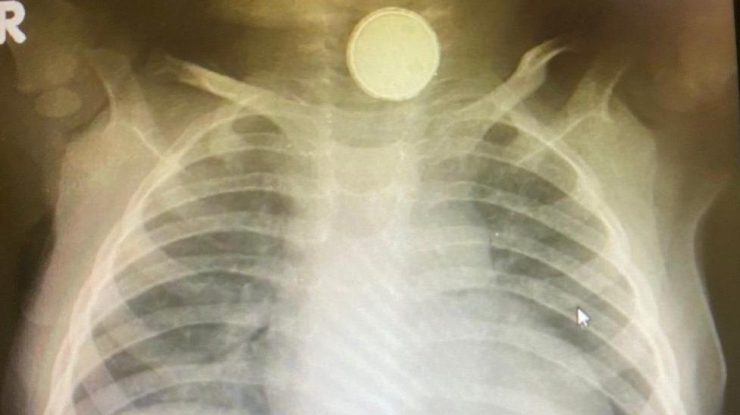

După o altă vizită la spital, în luna mai, fetiţei i s-a făcut o radiografie care a arătat că bateria blocată în esofagul ei cauzase probleme grave, deoarece era ruginită.

Iniţial, medicii au crezut că fetiţa de 11 luni are amigdalită sau o infecţie virală, până când o radiografie a arătat că în esofagul ei era blocată o baterie cu diametrul de 2,4 centimetri.